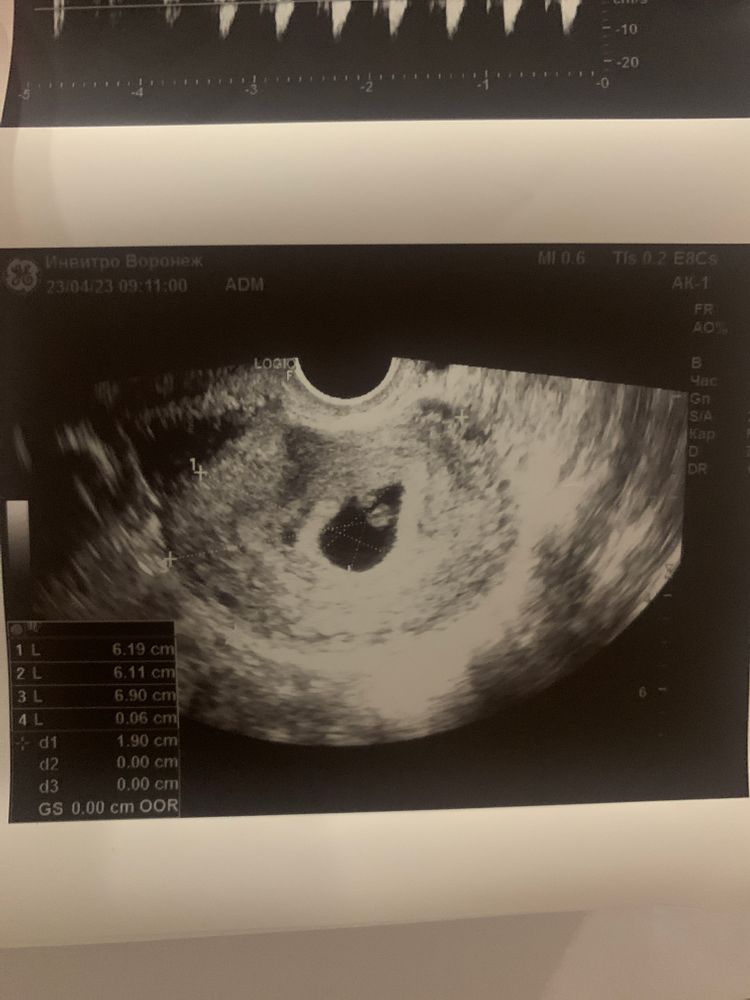

подскажите как быть ?! Стараюсь не думать и сохранять спокойствие , ходила на узи сказали 6.1 неделя , но отсутвует желтого мешочка( дословно не помню ) прописали прогестерон по 10 мг два раза в день - пью ! Сдаю кровь регулярно смотрю динамику хгч в 6.4 недели показатель - 64тыс , в 7 недель - 102 тыс , завтра 7,6 недель почти 8 пойду еще раз сдам на прием только 15 мая , сильный токсикоз ) чем чревато отсутствие желтого (мешочка) ?? Мне сказали что могут быть серьезнейщие патологии развития плода

Так на фото желточный мешочек есть,вы наверное путаете с желтым телом,а это вообще разные вещи

Непонятно о чём речь - о желточном мешочке или жёлтом теле? Скиньте текстовый протокол УЗИ! Там где написано про плодное яйцо и яичники..